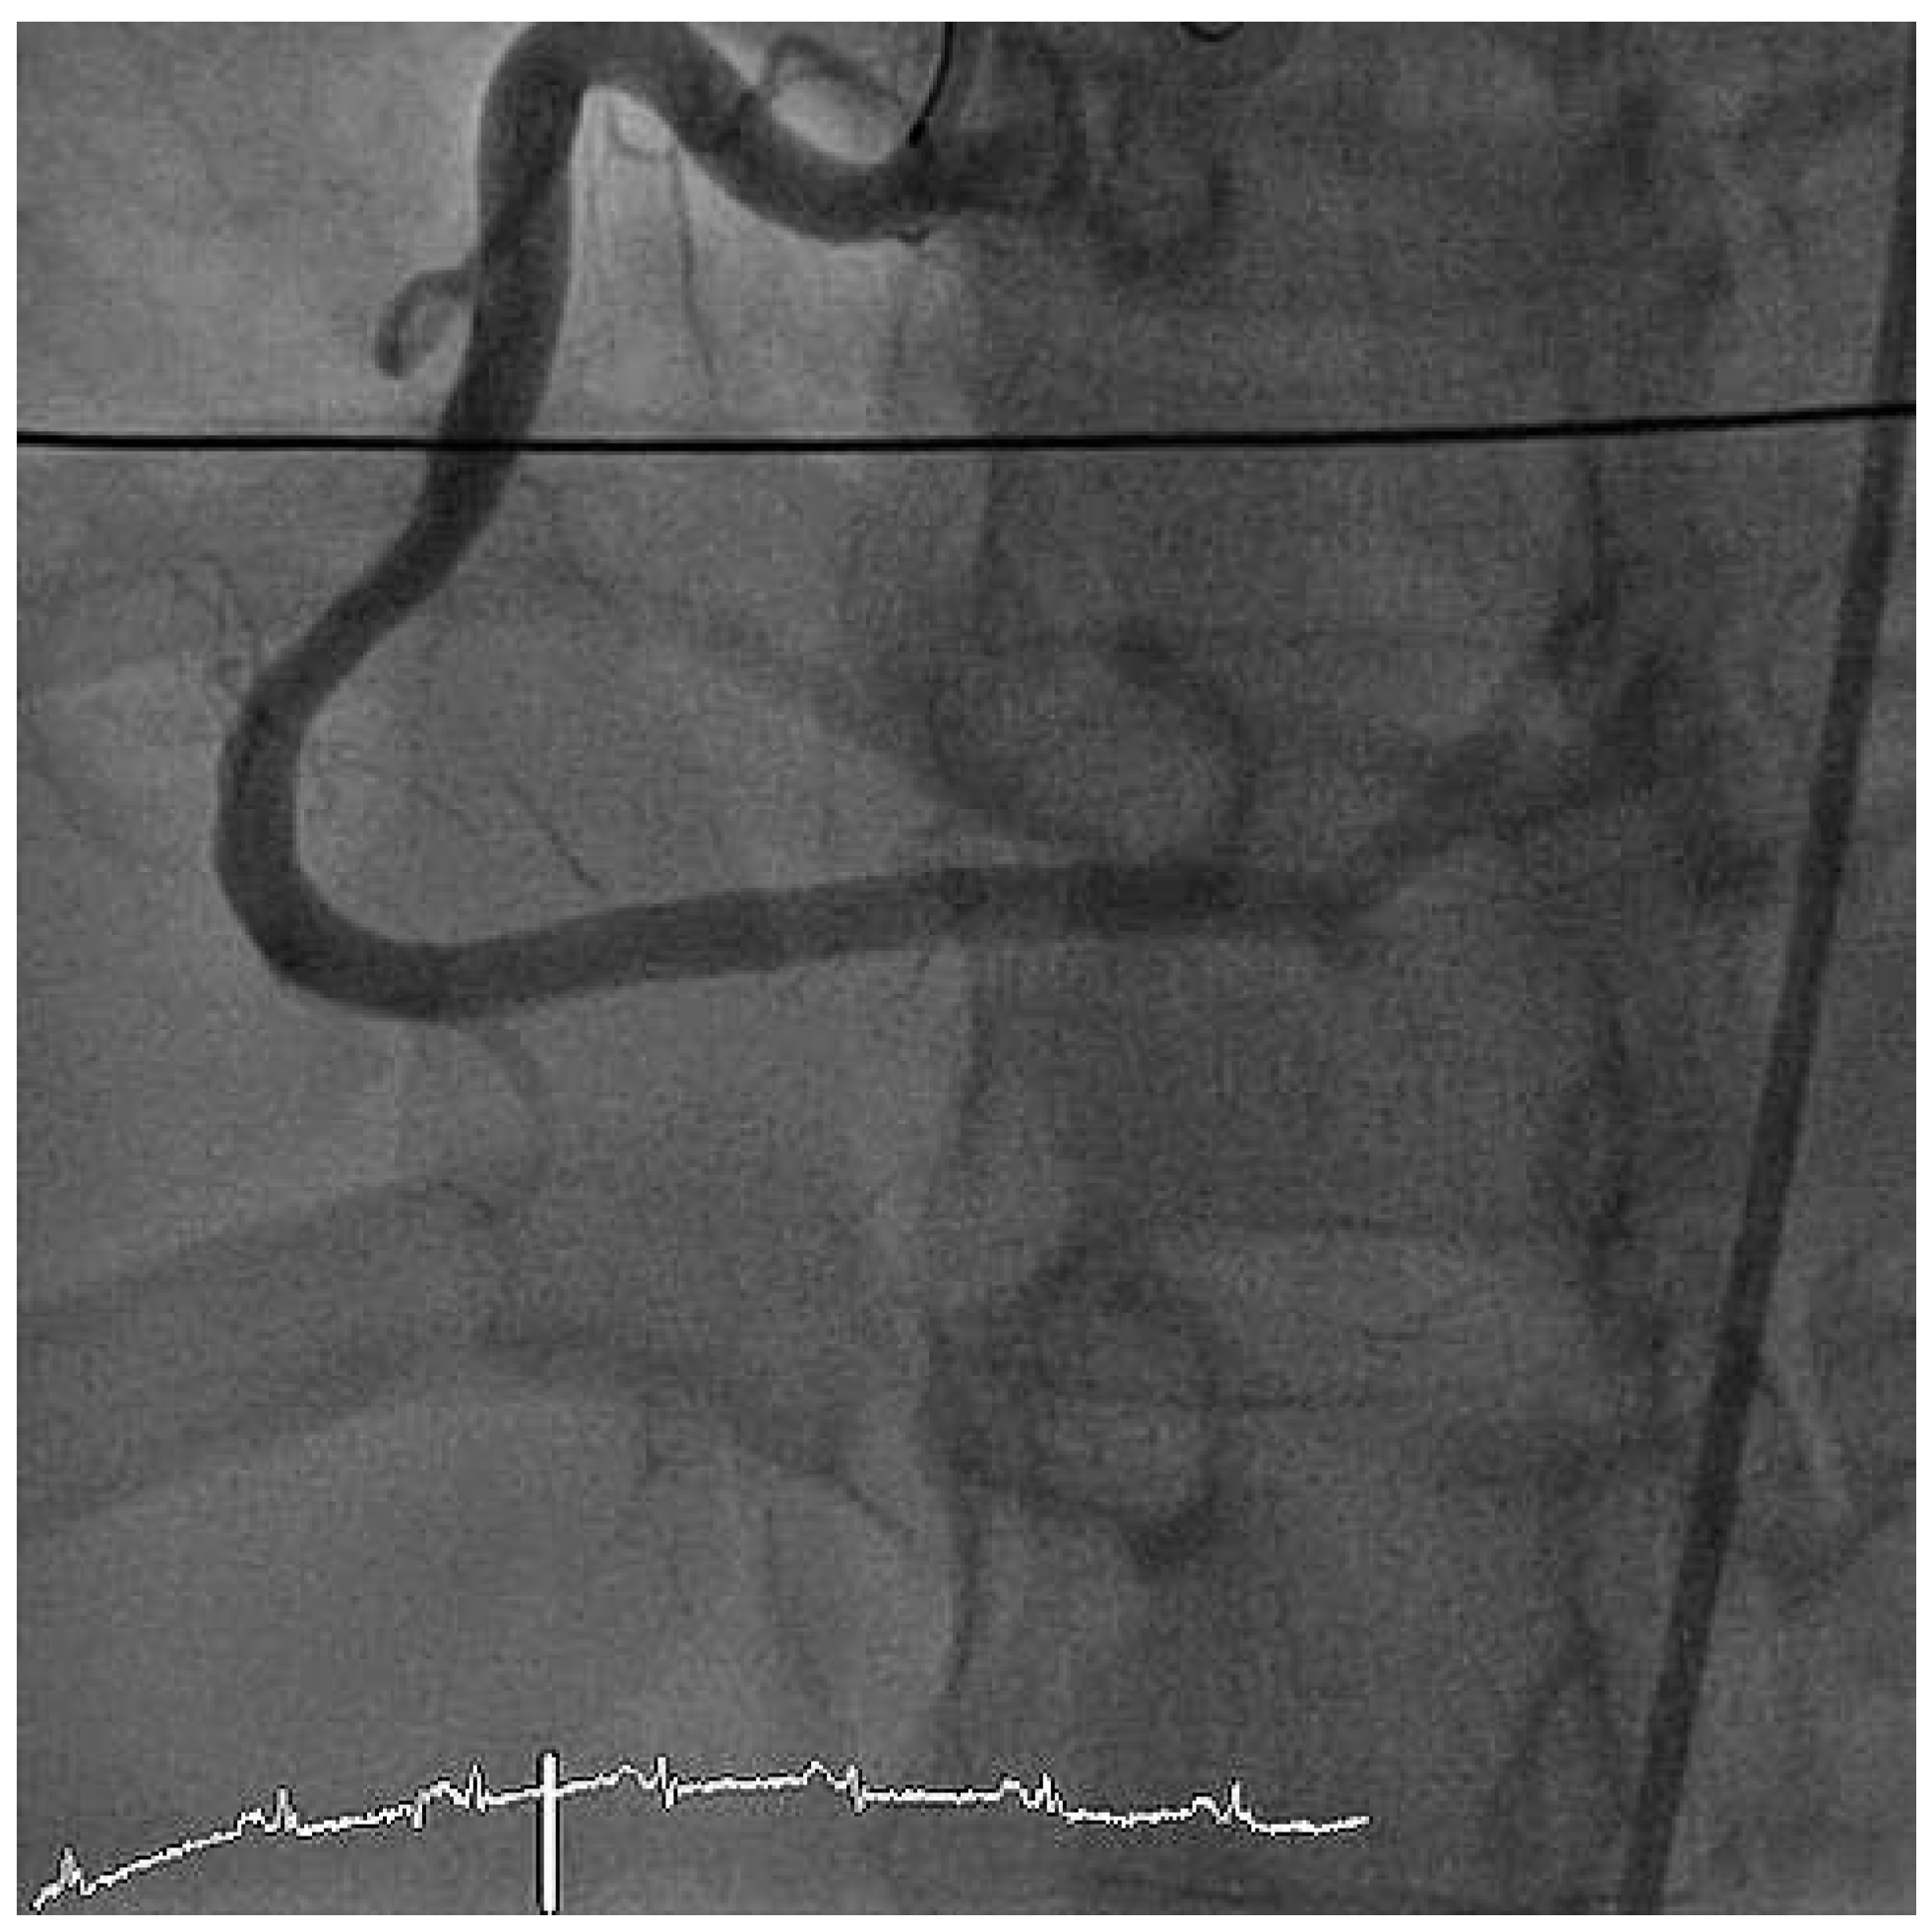

The ECG at admission showed normal sinus rhythm and ST-segment changes in the infero-lateral and the antero-septal leads (Figure 1). The initial troponin and CK-values were normal. Clinically the patient was in cardiogenic shock. Urgent invasive assessment revealed a severely depressed LV-function (EF 30%) with apical, anteroseptal and posterolateral akinesia. There was a total thrombotic occlusion of the mid LAD and the distal circumflex artery (Figure 2).

Figure 2. RAO view showing occlusion of the mid-LAD and of the left circumflex artery. LM = left main coronary artery; LAD = left anterior descending artery; LCX = left circumflex artery.